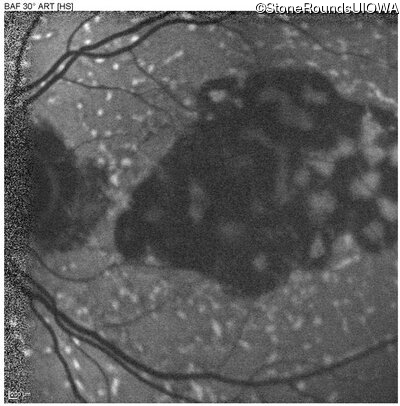

Blue Autofluorescence - Right - 20/25

Exemplar

Blue Autofluorescence - Left - 20/25 -2